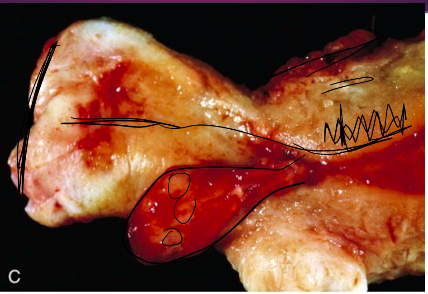

Describe the layers of the uterus as seen below

The body of the uterus is composed of three layers, the inner most endometrium (which is sloughed during menses), the muscular myometrium, and the outer perimetrium. Circled in this picture is the basal layer of the endometrium